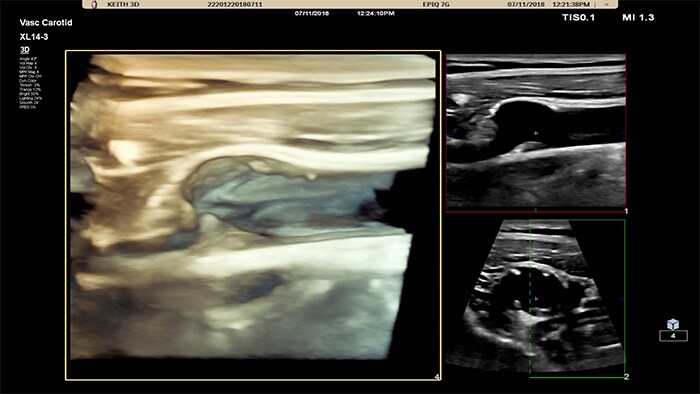

Imágenes xPlane

El transductor XL14-3 xMATRIX ofrece una adquisición de imágenes xPlane que supera al sistema convencional para exploraciones vasculares, pues ofrece imágenes en tiempo real tanto en los planos longitudinal como transversal de forma simultánea. La ventaja principal: las imágenes xPlane eliminan la necesidad de girar el transductor para adquirir vistas ortogonales. Basta con mover la esfera para realizar una evaluación anatómica completa, con lo que se ahorra tiempo en la exploración.

Doppler xPlane

El XL14-3 xMatrix también ofrece funciones de Doppler xPlane. El Doppler pulsado xPlane permite una colocación precisa del volumen de muestra mediante Doppler a través de imágenes de referencia longitudinales y transversales. La principal ventaja: el Doppler xPlane reduce los errores de colocación del volumen de muestra y ofrece una mayor reproducibilidad y coherencia a la hora de tomar muestras de estenosis pronunciadas.